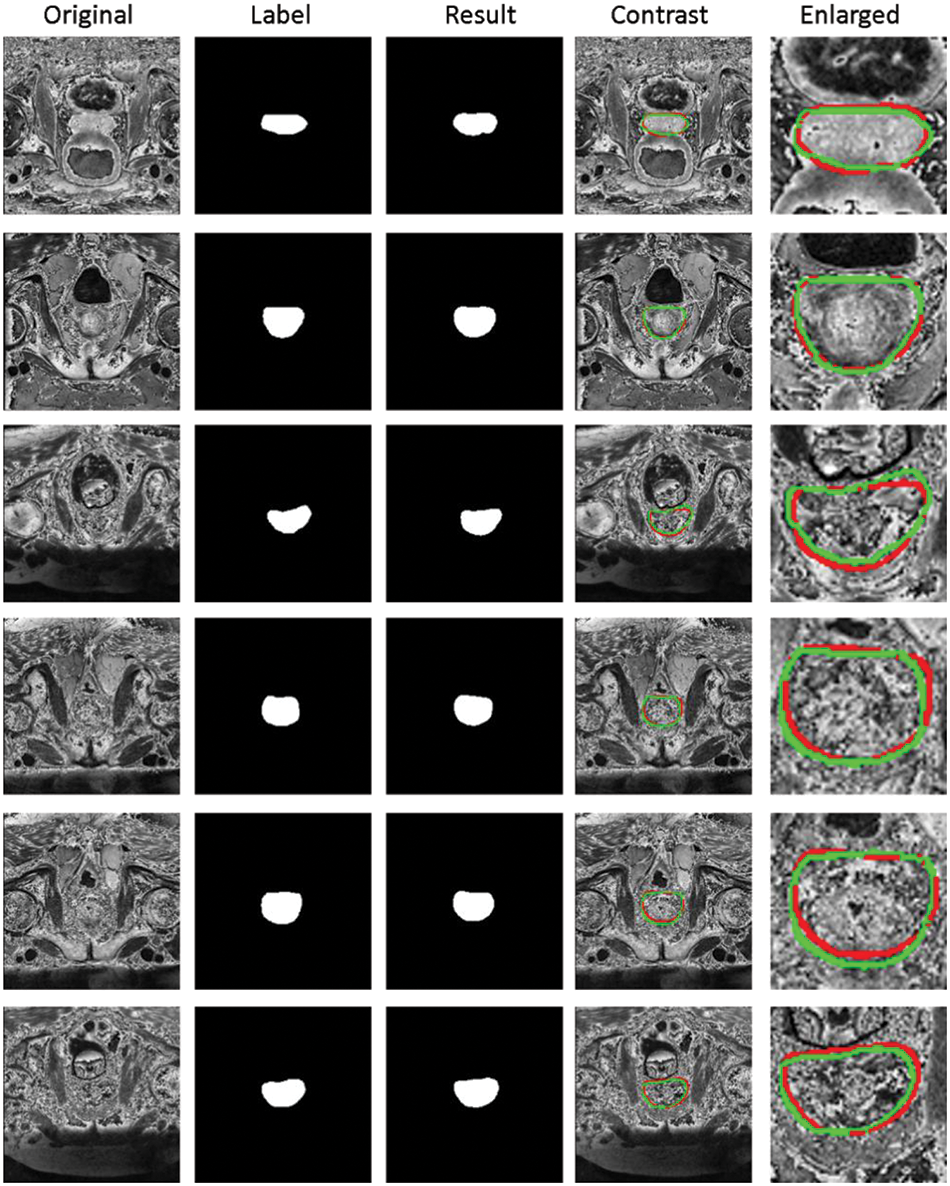

Fig. 5 shows the segmentation results of our method. The first column represents the original MRI image of the prostate. The second column represents the annotated image of the prostate by a doctor (as the ground truth). The third column represents the results of our method. The fourth column represents the comparison display of results and marks on the original drawing, the red line represents the result of our method, and the green line represents the ground truth. The fourth image’s magnified picture of the prostate’s major region is depicted in the fifth column. As illustrated in Fig. 5, our segmentation results are highly correlated with the prostate area annotated. The prostate lacks clear margins and complex background textures between the prostate and other anatomical structures, whereas the size, shape, and intensity distribution of the prostate have changed significantly. On the other hand, as column 5 of Fig. 5 shows, our approach performed well in border processing of the MRI images.

Figure 5: Segmentation results of prostate region of our method. First column: Original MRI image of prostate. Second column: The annotated image of the prostate by the doctor (as the ground truth). Third column: The results of our method. Fourth column: Comparison display of results and marks on the original drawing, the red line represents the result of our method, and the green line represents the ground truth. Fifth column: Enlarged view of the main prostate area on the fourth image